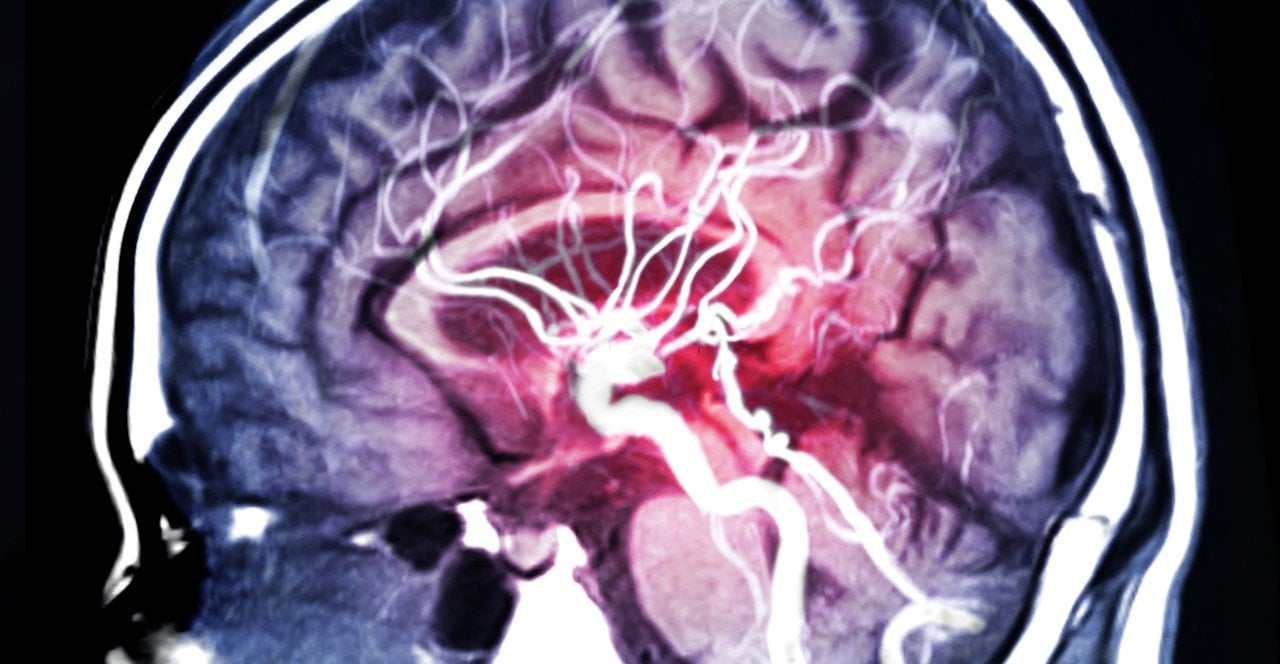

Les victimes d’un Accident Vasculaire Cérébrale ont en moyenne 74 ans. Ce chiffre fait souvent oublier que tous les âges sont concernés par cette urgence vitale. Margot Turcat, qui a fait un AVC ischémique à 33 ans, témoigne dans les pages du Huffington Post pour rappeler cette réalité.

"Les secours sont longs, on ne me croit pas alors que je dis et martèle que j’ai tous les signes cliniques de l’AVC, mais grâce à mon père qui est arrivé le plus vite possible à la maison et qui a insisté lourdement, je suis évacuée au CHU de Bordeaux afin que je passe une IRM. Le verdict tombe, sans appel : AVC ischémique !”. Il s’agit d’un caillot qui bouche un vaisseau sanguin du cerveau, privant certaines zones d’oxygène et de nutriments.